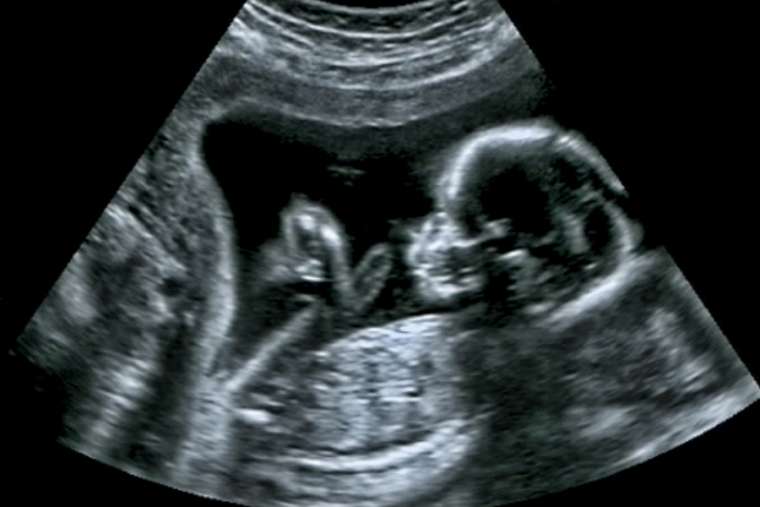

Un nuevo estudio muestra que ya existen diferencias entre el cerebro masculino y femenino en el útero

“Un nuevo estudio científicoˮ ha encontrado diferencias significativas en las formas en que los cerebros de los fetos masculinos y femeninos funcionan ya antes del nacimiento.